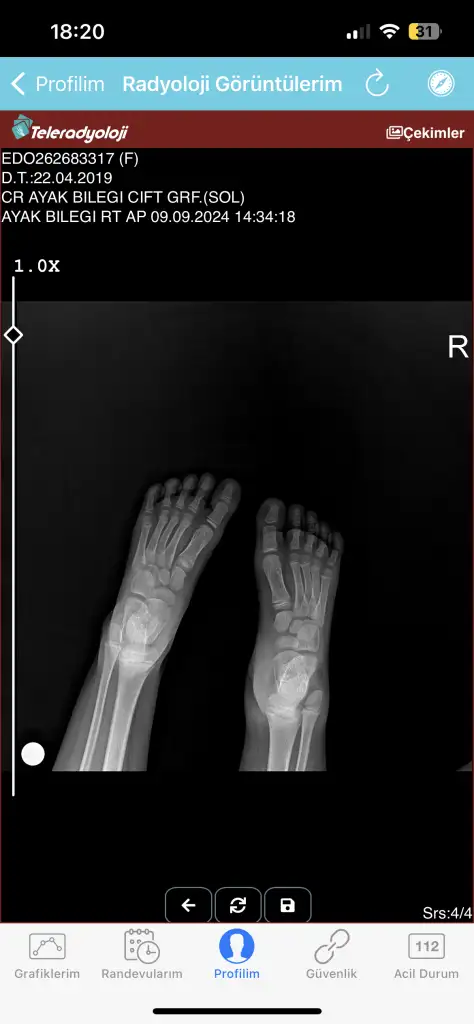

Merhaba benim kızım 4 gün önce bisikletten düştü ve ayağı yaralandı şişti doktora götürdüm doktor röntgen çekti röntgende pek bir şey görünmedi pansuman yapıp yolladılar iki gün sonra yani bugün pansumanını açtım ayağı daha kötü olmuş ve şişmişti kesinlikle üstüne basamıyor ve dokun durmuyor bugün yine gittim röntgen ve tomografi çekti tomografi raporunu ve röntgeni ekliyorum acaba anlayan bilen var mı bilen varsa yazabilir mi rica etsem ayağı çok kötü durumda çünkü korkuyorum bir şey olur diye